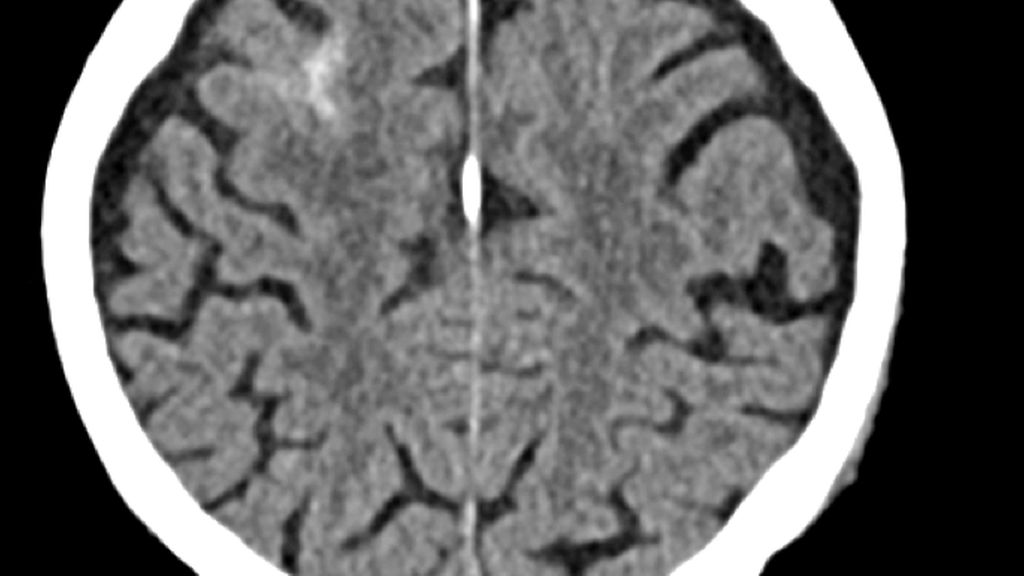

Abb. 1: 88-jähriger männlicher Patient erleidet unter der Einnahme von Rivaroxaban (Xarelto®) im Rahmen eines häuslichen Sturzes eine Subarachnoidalblutung rechts frontal

Dieser epidemiologische Hintergrund spiegelt sich im klinischen Alltag wider. Die Behandlung von Patient*innen mit leichtem SHT unter laufender oraler Antikoagulation ist eine alltägliche Situation für jede Traumatologin und jeden Traumatologen in der Notfallambulanz. Die intrakranielle Hämorrhagie stellt dabei eine gefürchtete Folge dar (Abb.1). Das erhöhte Risiko für intrakranielle Blutungen bei Vitamin-K-Antagonisten (VKA) wurde bereits vor Langem nachgewiesen, durch die Einführung der direkten oralen Antikoagulanzien (DOAK) geraten die VKA jedoch immer mehr in den Hintergrund.4,5